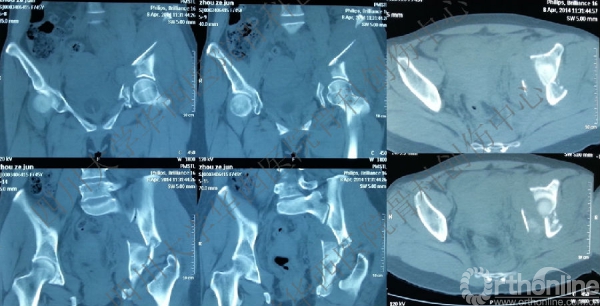

术前CT

入院后行左股骨髁上牵引,积极术前准备,做CT,证实双柱骨折的诊断。

术前三维CT

做三维重建,进一步为手术做术前详细的计划,决定前方入路。